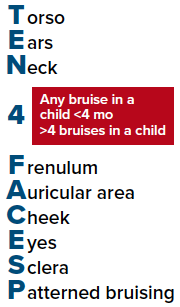

With all cases of suspected non-accidental trauma, emergency physicians should initiate a work-up to assess for other injuries. In young children, this evaluation often includes a detailed history and a physical examination, radiographs, and laboratory testing including a CBC with differential, AST, ALT, lipase level, and a urinalysis.2 Depending on the type of injuries observed (ie, bruising, fractures, intracranial injury), further testing may be indicated. In cases of bruising, a hematological work up (PT/PTT/INR, Fibrinogen, vWF Ag, VWF activity, Factors 8 and 9) should be considered to rule out any bleeding disorders confounding exam findings. Head imaging should be obtained in the event the child is less than six months old, or there is evidence of head/facial trauma, or if the patient has an abnormal neurologic exam. An abdominal CT may be indicated if laboratory values or physical exam are concerning for occult hepatic or pancreatic injury.2 Finally, in non-skull fractures, calcium, phosphorus, Vit D, intact PTH, and alkaline phosphatase levels should be obtained. A skeletal survey (SS) should be obtained in all children less than 2 years of age with a suspicious injury. The use of skeletal surveys in children 2-5 years of age varies widely, with some cases reporting 36-45% of these patients receive a skeletal survey in the case of suspected non-accidental trauma.3 This is likely due to the fact that most sources recommend that the decision about obtaining a SS in the 2- to 5-year-old age group must be made individually on the basis of the specific clinical indicators of abuse, such as bruises in the TEN 4 FACES region, as well as any high specificity fractures, such as classic metaphyseal lesions (CMLs), rib fractures (especially posteromedial), scapular fractures, spinous process fractures, and sternal fractures.5-7 Multiple fractures, fractures of different ages, and complex skull fractures are of moderate specificity for NAT, but again may necessitate the need for a skeletal survey on a case-by-case basis.7

Figure 1. Body region- and age-based bruising clinical decision rule to identify children who are at high risk for abuse and require further evaluation4